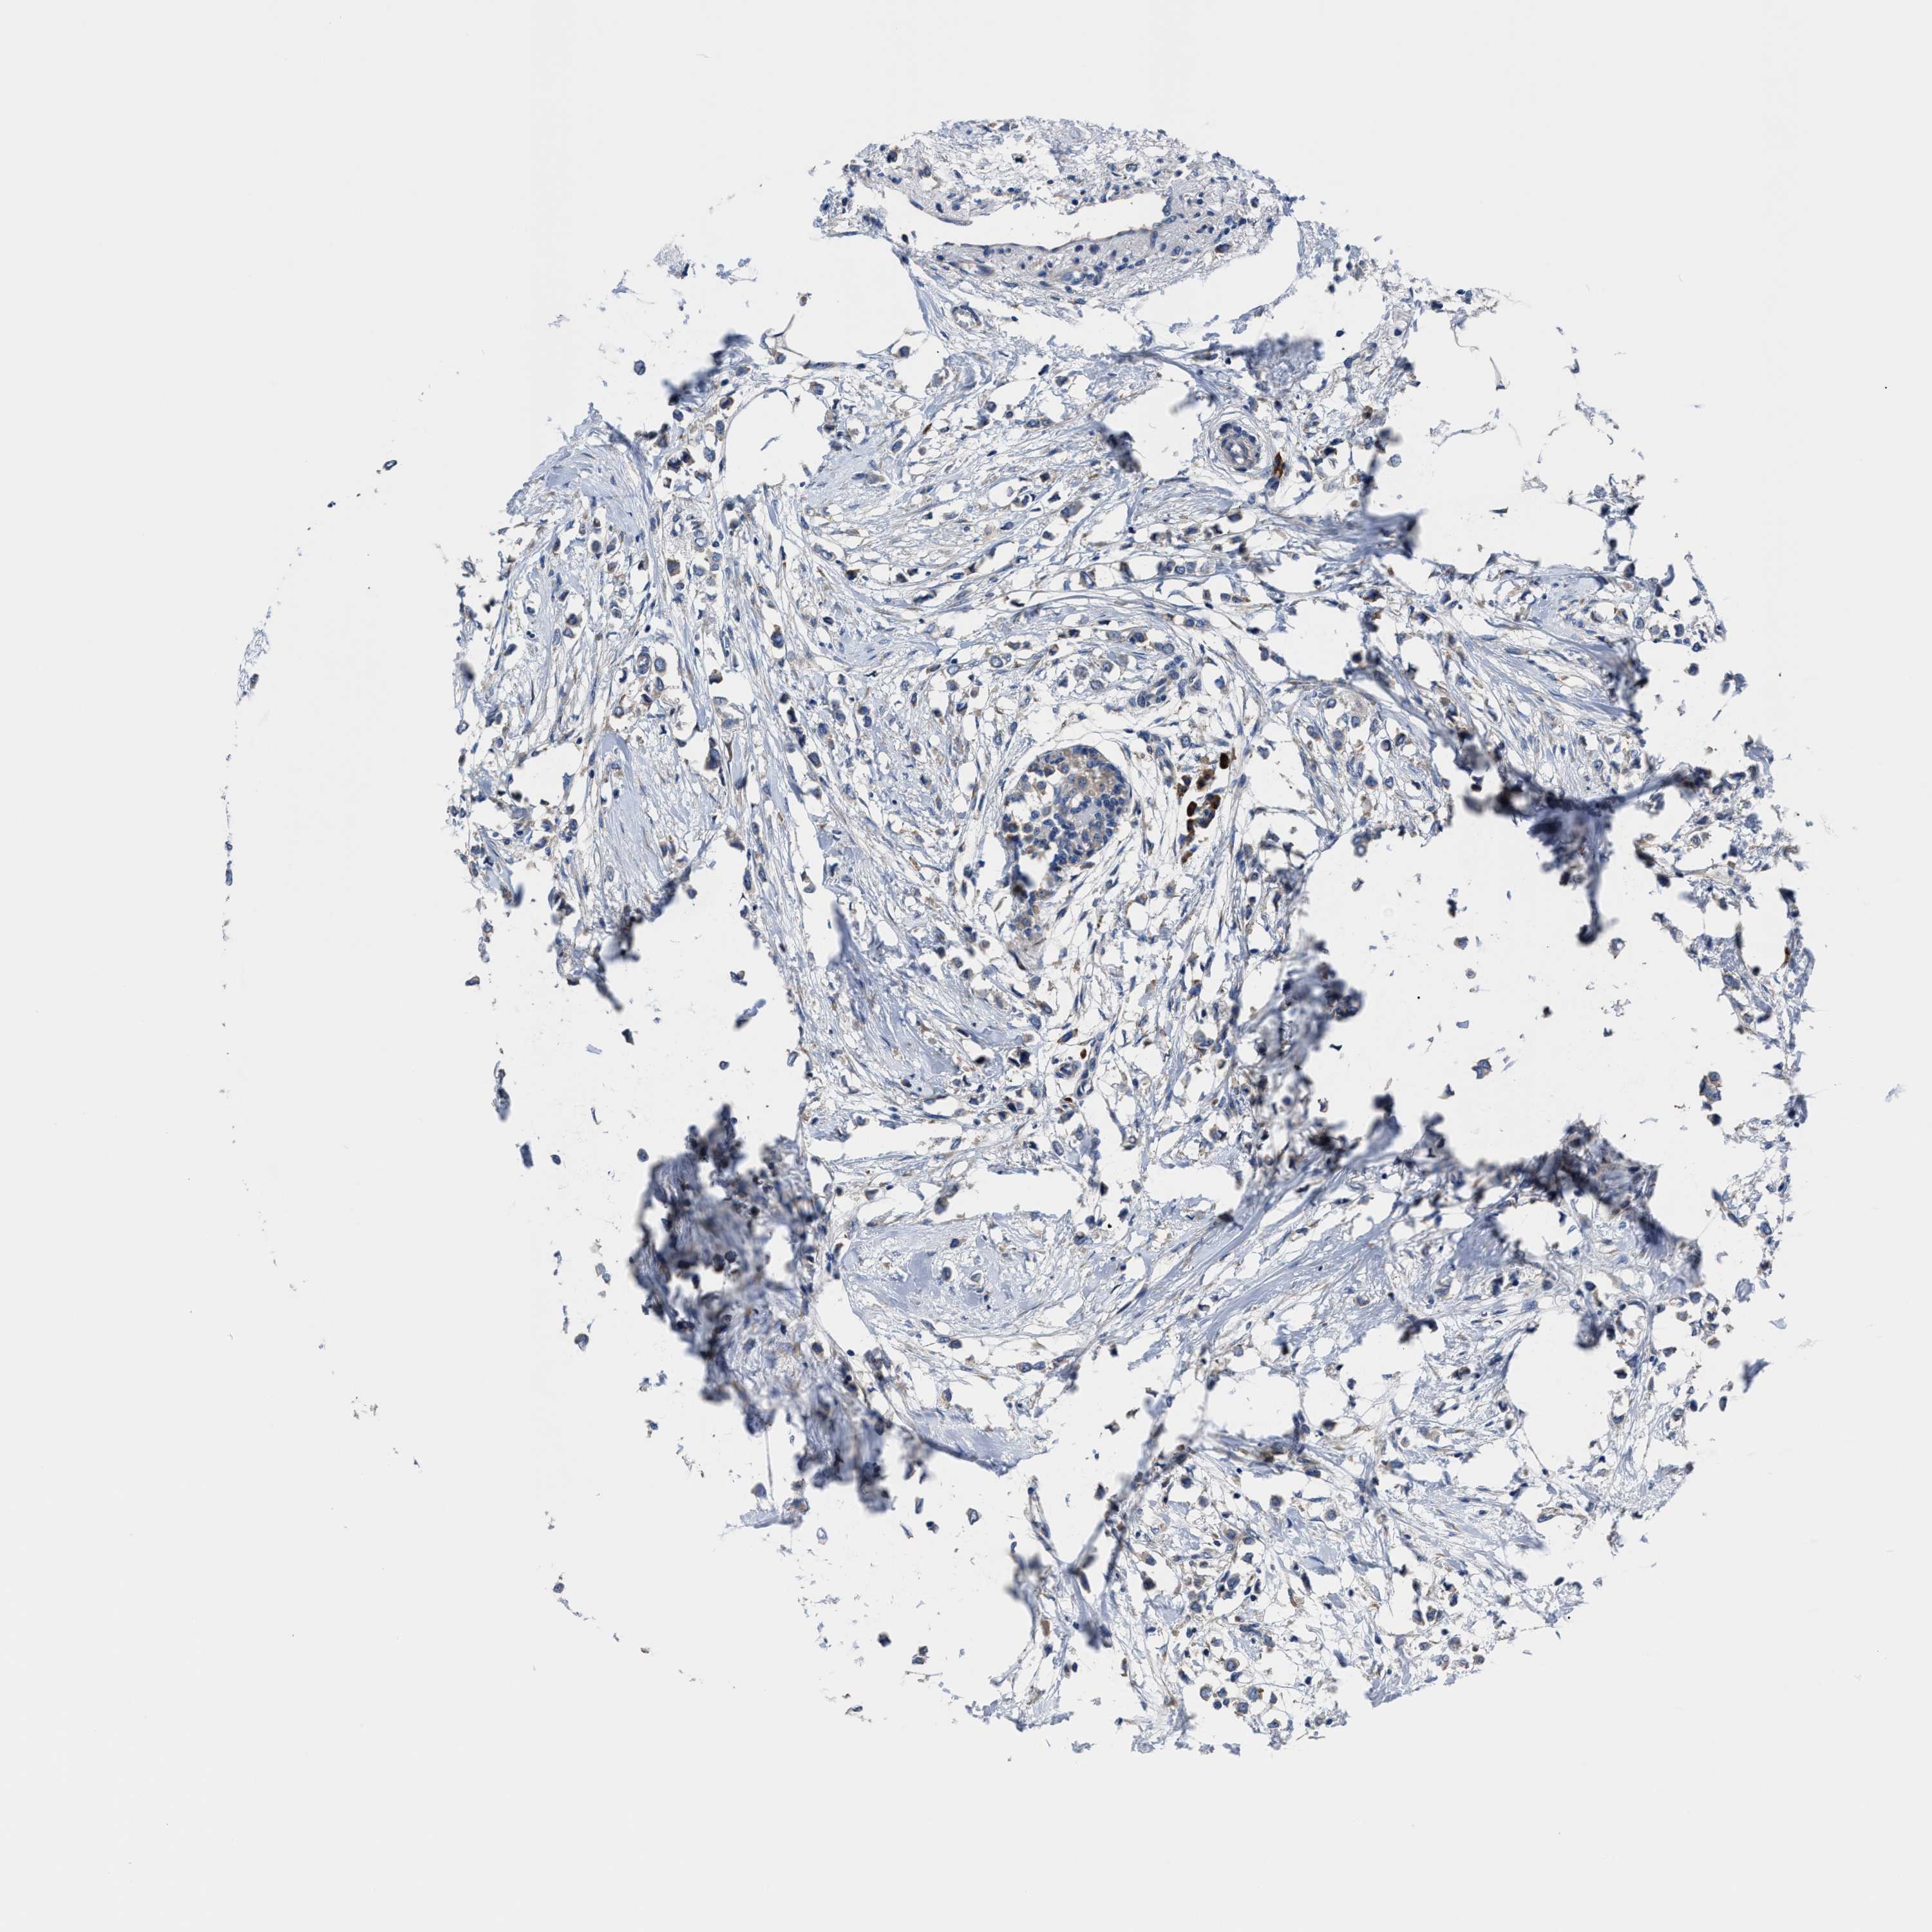

BRCA TCGA BRCA VALIDATION PROTEIN EXPRESSION